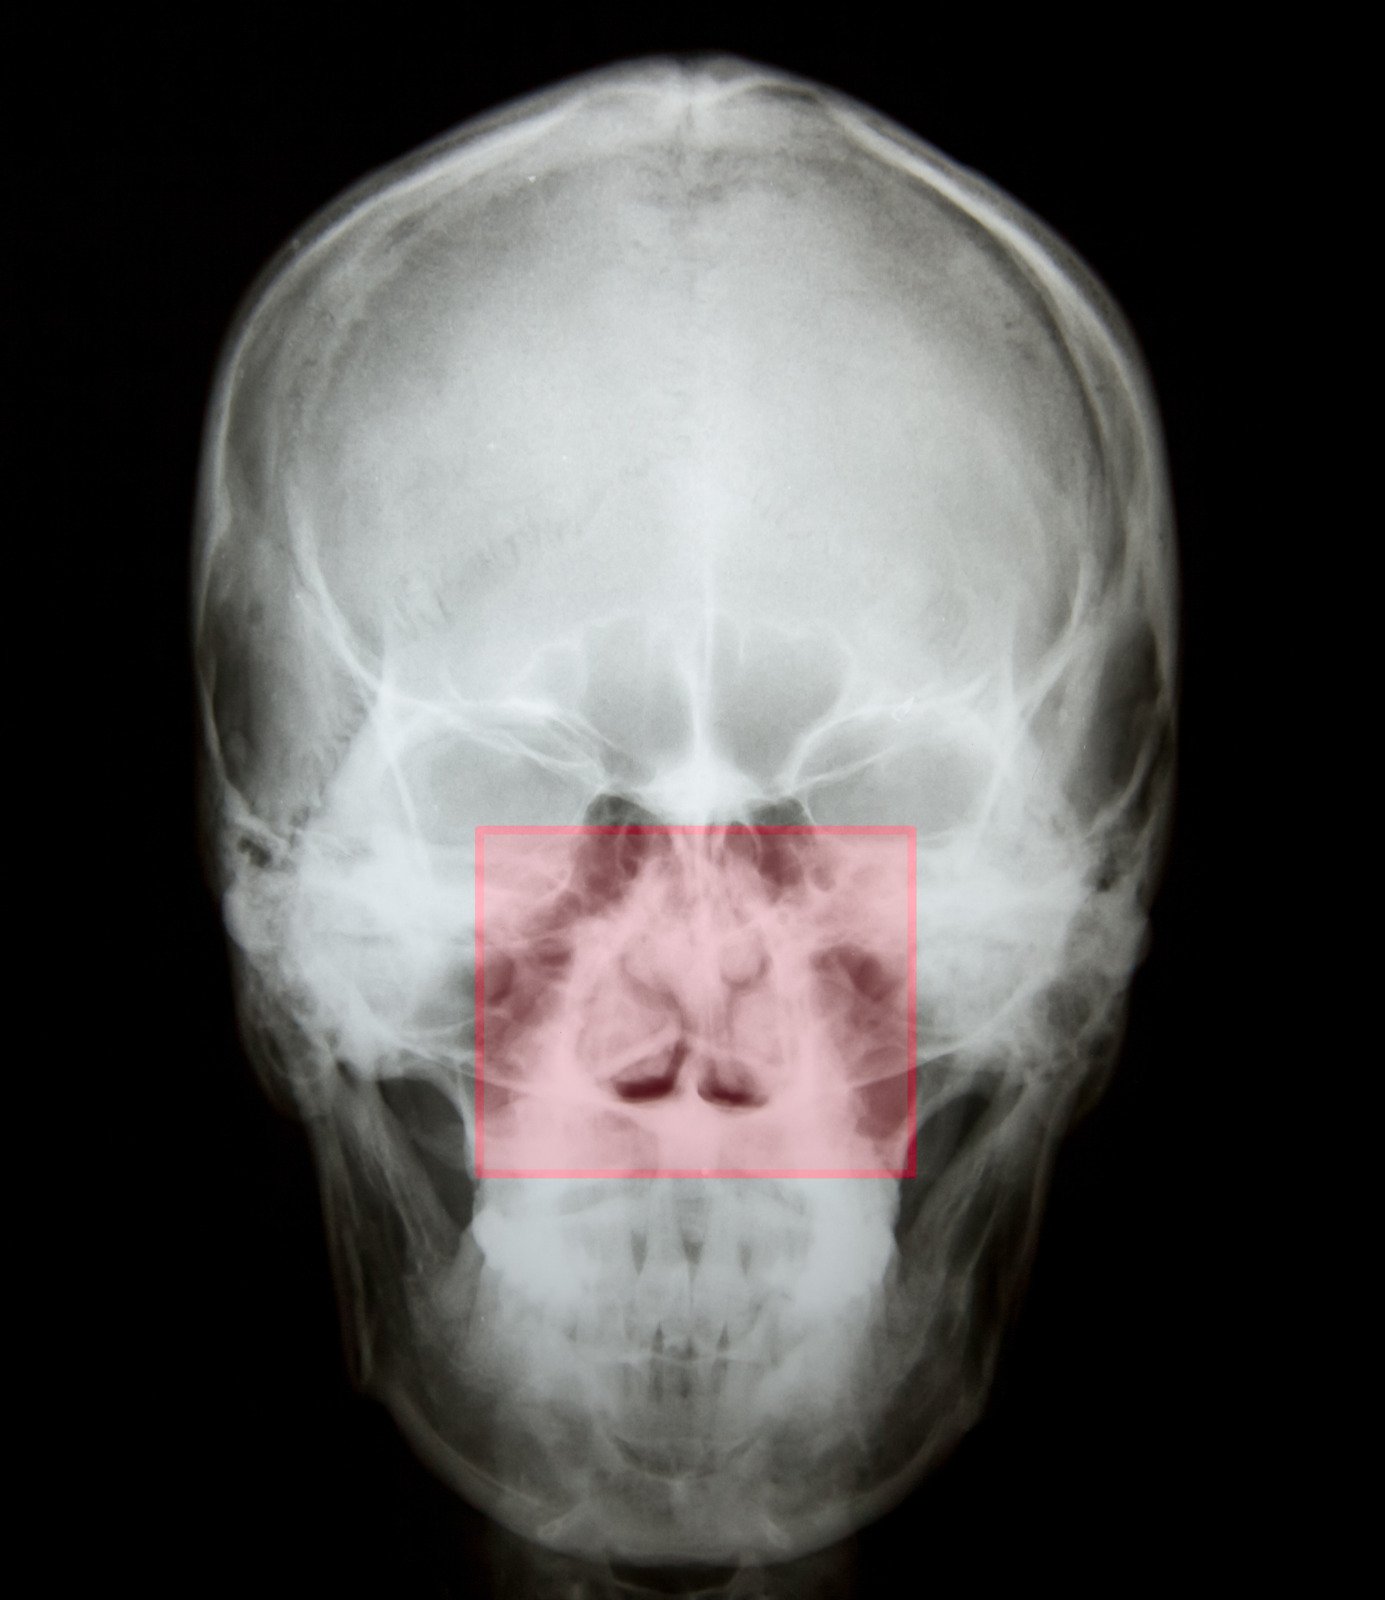

비중격 성형술(Septoplasty)는 코 안을 좌우로 나누는 비중격(Septum)이 휘어져(비중격 만곡) 코막힘, 부비동염 등의 증상을 유발하는 경우 이를 교정하는 수술적 치료입니다.

비경검사(Nasal Endoscopy), CT 스캔 등을 통해 비중격의 상태와 코 내부 구조를 평가.